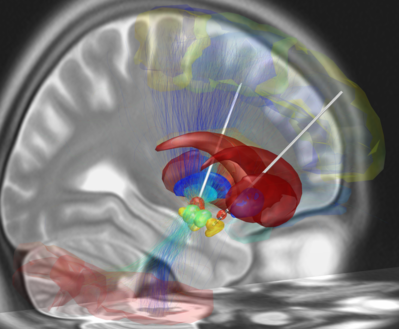

Die Stimulationsparameter werden von einem Computer gesteuert, um Amplituden, Frequenzen und Impulsbreiten anzupassen. Häufige Ziele für THS bei Parkinson sind der Nucleus subthalamicus, der Globus pallidus interna und der ventrale intermediäre Kern des Thalamus.

Neue Entwicklungen, wie richtungsweisende THS-Elektroden, helfen, die Stromausbreitung auf Strukturen zu vermeiden, die Nebenwirkungen verursachen könnten. Die Kontrolle des Stroms zu einzelnen Kontakten auf einer THS-Elektrode ermöglicht es, das elektrische Feld zwischen mehreren aktiven Kontakten zu formen. Diese Fortschritte machen THS zu einer effektiven Behandlungsoption.